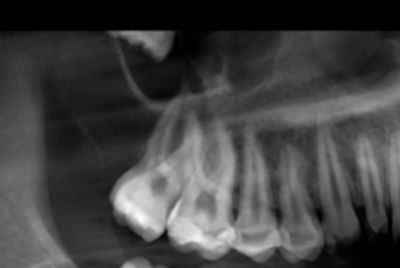

15-year-old girl with an unusual posterior maxillary lesion

A 15-year-old girl was referred to the oral surgeon by her family dentist because of an unusual lesion in her posterior right maxilla.